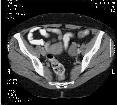

Una imagen radiologica suele tener entre 256x256x1 hasta 8192x4096x2, es facil entender ese "derroche" de Gigas para su almacenamiento, ademas se prevee que solo aguantara unos 6 meses, pasado ese tiempo un estudio de un paciente pasa a otro soporte (amovible), de momento cinta DAT, pero seguramente se cambiara a robots de Magneto Opticos de 600G.

Para un paciente determinado se pueden presentar X exploraciones de varias modalidades. Una exploracion es un examen radiologico, un examen puede tener una o X imagenes o disparos. Una modalidad es un aparato capaz de producir imagenes radiologicas sea por Rayos-X, ultrasonidos, resonancia magnetica, etc...

Segun las pruebas realizadas una imagen de 512x512x2 tarda 0.3 segundos, de promedio, en mostrarse en pantalla desde que se inicio la transaccion. Hablo de promedio, porque un estudio no es siempre una sola imagen, este promedio es mejorable y no solo por hard sino por la propia forma de obtenerlo.